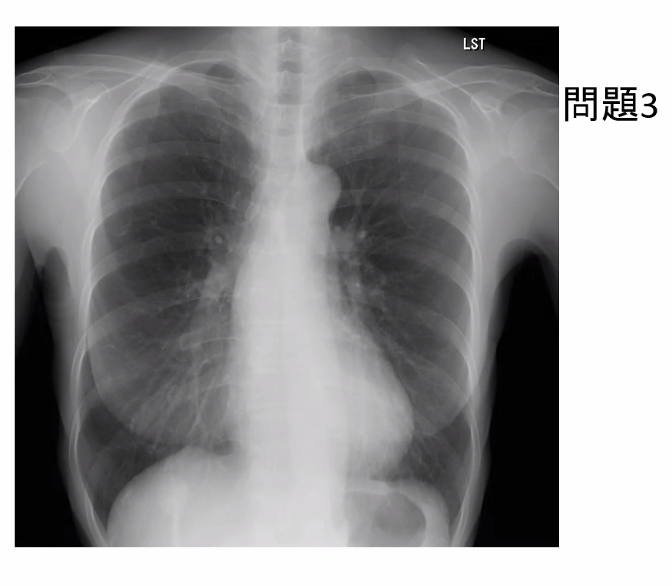

胸部X線で見落としやすい場所

あなたも聞いたことがあるかもしれませんが、胸部レントゲンでは特に見落としやすい部位があります。

それは下図のところ。

これらの部位は左右差を見たり、以前のレントゲン写真があれば比べてみたりと、目を皿のようにして、しつこく見ていく必要があります。

ここで問題を一つ。

前回(2025年12月11日)の記事に載せた写真は、井上先生からのクイズの中の一つですが、異常陰影はどこにあるか考えてみて下さい。

あなたは分かりましたか?